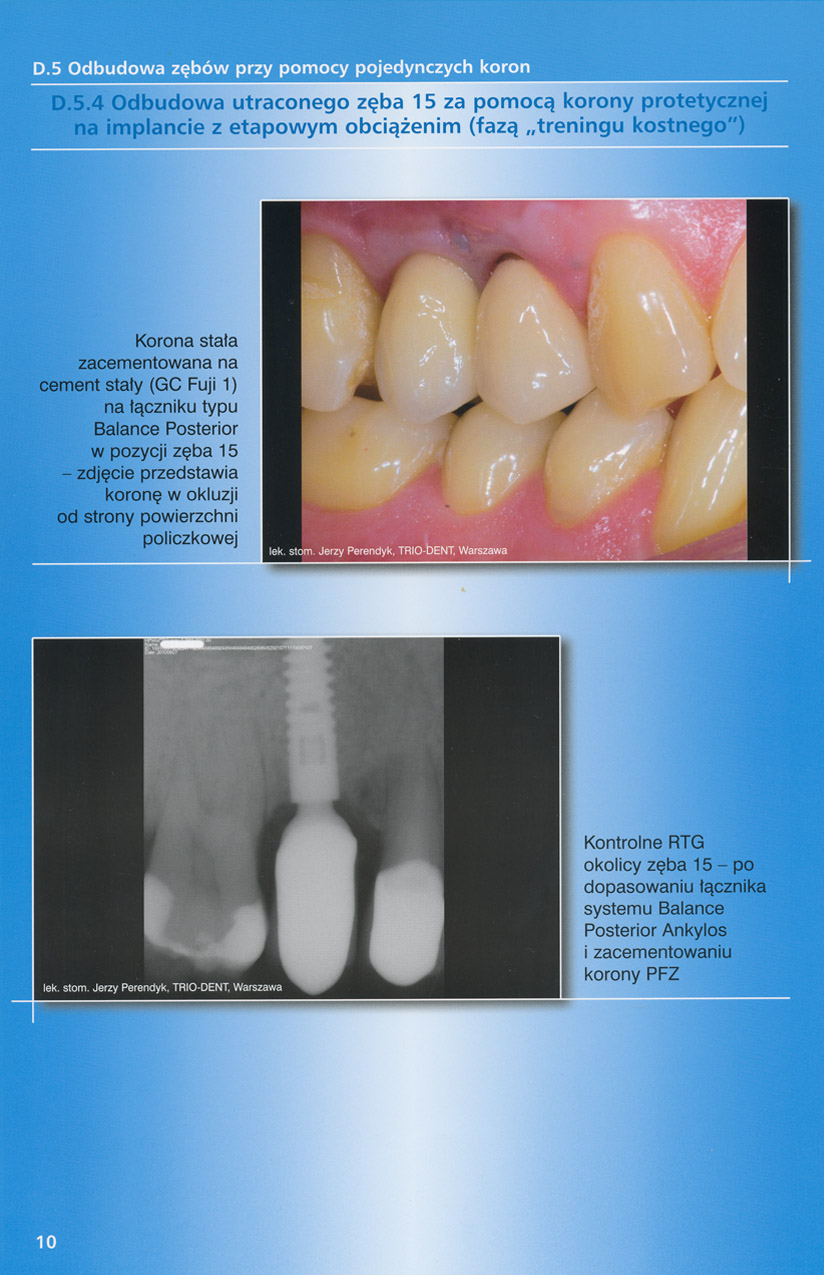

zobacz więcejGaleria przypadków klinicznych, obrazująca proces terapeutyczny od stanu wyjściowego aż do oddania ostatecznej pracy uzupełnienia brakującego uzębienia.